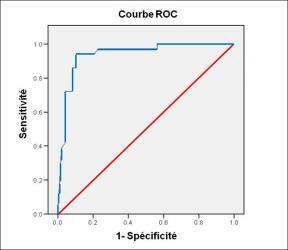

Performance diagnostique de l’interféron gamma dans l’identification de l’origine tuberculeuse des pleurésies exsudatives